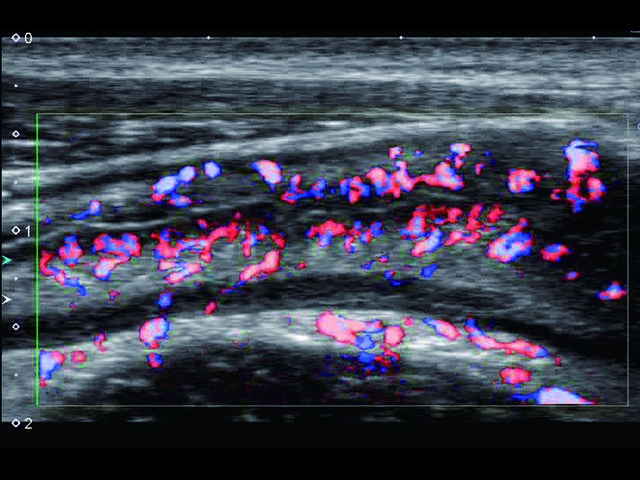

Обновленная версия легендарного УЗ-сканера. Стационарный аппарат экспертного класса Aplio 500 Toshiba NEW, визуализирует анатомические структуры в высоком разрешении. Модель позволяет выявить микрокальцификаты, новообразования, нарушения в работе сердца, сосудов и мышц. Присутствует функция виртуальной эндоскопии, 4D-сканирования, эластометрии тканей, УЗИ с контрастированием. За повышение качества изображения отвечают технологии ApliPure и Superb Microvascular Imaging. Первая задействует возможности пространственного и частотного кодирования, формирует цельный визуальный ряд с сохранением клинических маркеров. Вторая улучшает отображение микрососудистого русла, используя доплеровский эффект. Модель оснащена 21-дюймовым монитором, имеет 4 активных порта. Возможно подключение педиатрических, интраоперационных, лапароскопических и чреспищеводных датчиков.

• SMI. Опция, упрощающая визуализацию микроциркуляторного русла. С ее помощью обследуются сосуды с низкой интенсивностью кровотока, изучаются наиболее тонкие структуры. SMI упрощает диагностику новообразований, минимизирует вероятность ошибки.